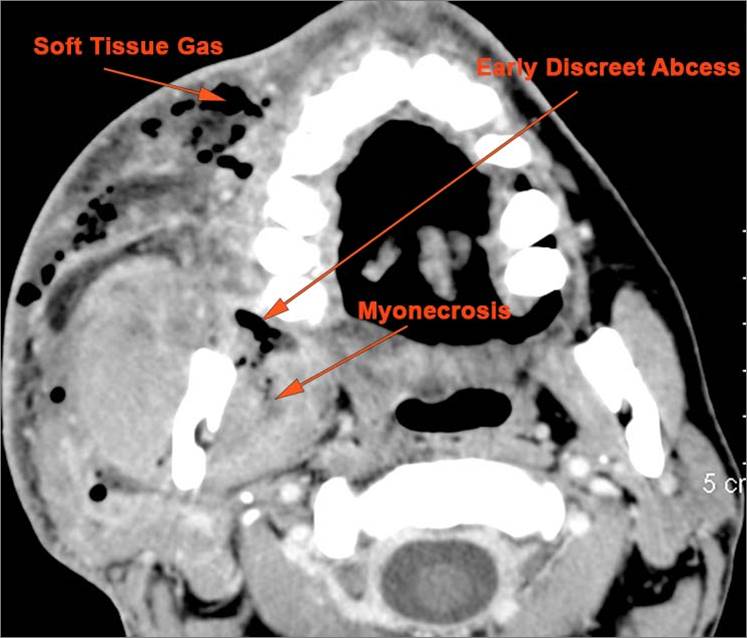

​There is general or localized soft tissue swelling of the superficial or deep neck soft tissues.

There is gas in the soft tissues.

There is edema/abscess within or surrounding the buccal space, masticator space, floor of the mouth, submandibular space or the adjacent superficial fascia or subcutaneous fat and skin.